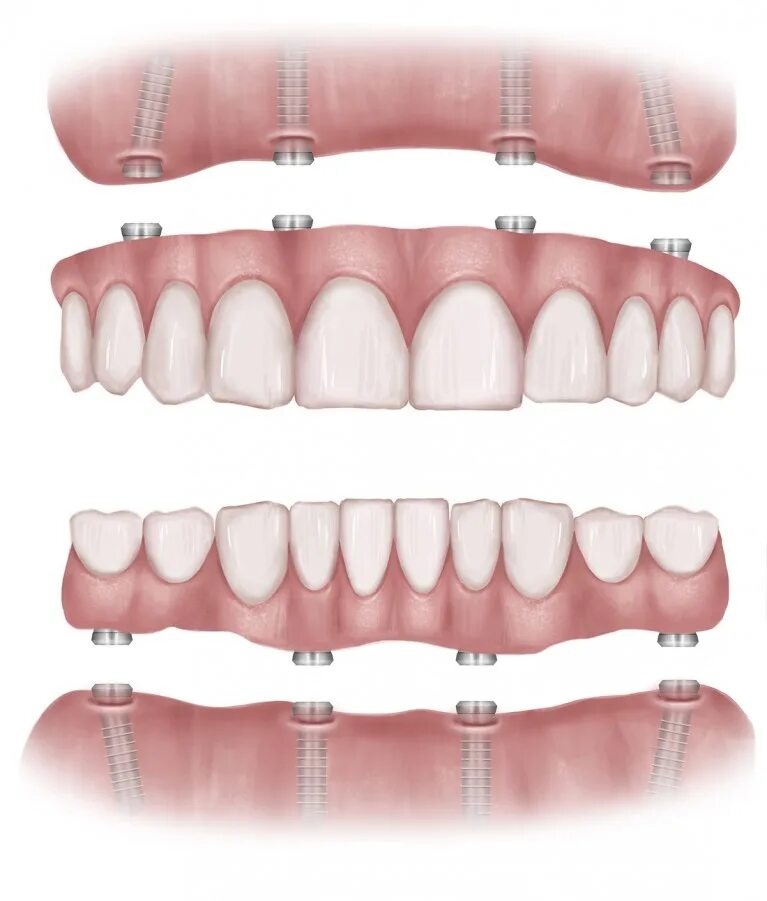

Поставить 4 зуба